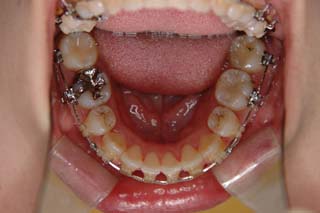

使用した主な装置名:TPB、マルチブラケット装置、オーソアンカー SMAPシステム

一般的なマルチブラケット装置を用いた治療では、先ずは形状記憶合金のワイヤーで大まかに配列を行い、バネをきかせたワイヤー、堅いワイヤーを使って仕上げていく方法です。

最終仕上げの段階です。かなり太めのワイヤーが入っていますが、このワイヤーの後にオーバーコレクション(元々の歯の捻れが有った場合、後戻りで出てきやすいので、わざと過剰に捻れを治しておく事)を行うための、細めのワイヤーを使う事もあります。